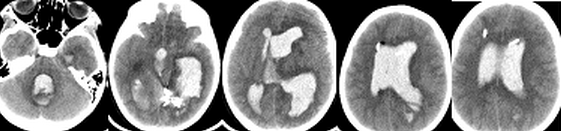

(проведение ИГ для коррекции ВЧГ у пациентки с внутримозговой гематомой и прорывом крови в желудочковую систему. Пациентка Т, 8 лет, поступила в Институт с диагнозом: Артерио-венозная мальформация левой теменно-височной области. У пациентки выявлялся судорожный синдром, резистентный к проводимой терапии аниконвульсантами. Очаговой неврологической симптоматики не было. Во время эндовазальной эмболизации АВМ, после ее частичной окклюзии, произошел разрыв мальформации с прорывом крови в желудочковую систему. Был установлен наружный вентрикулярный дренаж в левый боковой желудочек, и пациентка переведена в отделение реанимации в состоянии седации на ИВЛ. Зрачки были узкими. При КТ головного мозга выявлена гемотампонада желудочковой системы. Исходя из полученных при КТ данных, был установлен наружный вентрикулярный дренаж в правый боковой желудочек и паренхиматозный датчик ВЧД (Codman, USA) (Рисунок 2). В связи с внутричерепной гипертензией (ВЧД: 25-35 мм.рт.ст.) и неэффективностью осмотерапии было принято решение о проведении ИГ по выше приведенному протоколу. Целевая температура была достигнута через 2 часа после начала охлаждения. В течение суток удавалось поддерживать нормальные значения ВЧД, несмотря на выраженную гемотампонаду желудочков. На вторые сутки развилась устойчивая ВЧГ и произошло вклинение. Гипотермия и седация были прекращены, верифицирована смерть мозга. Пациентка скончалась на 7 сутки после операции.